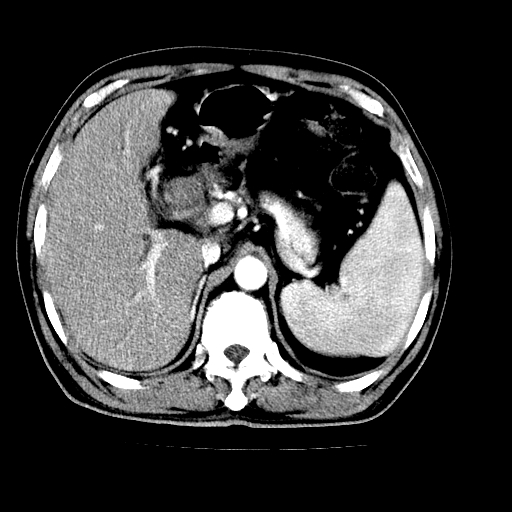

男,66岁,上腹部不适、黄染一周。彩超示:肝左叶占位,肝内胆管扩张,胆总管扩张,胆总管占位?

肝左叶不规则软组织肿块影,边缘不规整邻近肝实质受累分界不清;肝内胆管(左叶)明显扩张成“软藤状”,诊断:肝左叶胆管细胞癌。

左叶胆管细胞癌累及胆总管,门脉左支受侵,慢性胆囊炎胆结石,左肾小囊肿

支持肝左叶肝内胆管细胞癌伴胆总管及门脉左支受侵。

支持 1肝左叶肝内胆管细胞癌伴胆总管及门脉左支受侵。2胆囊钙乳症。